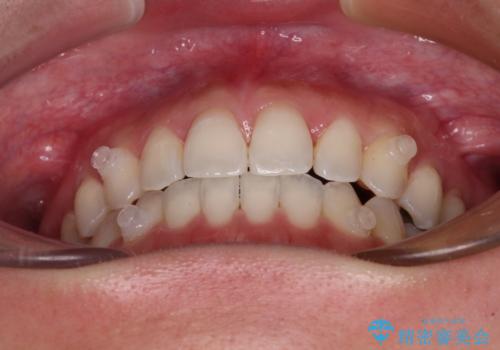

【モニター】狭い上顎歯列とオープンバイト 急速拡大装置を用いた矯正治療

- 前歯の開咬を気にして来院された患者様です。

上顎歯列が狭窄していたため、急速拡大装置により上顎骨を側方に拡大し、その後インビザラインにて矯正治療を行うこととしました。

舌の突出癖が開咬の原因であったので、改善のための舌トレーニングを行っていただきました。

舌トレーニングは後戻りにも大きく影響するため、とても重要なトレーニングです。